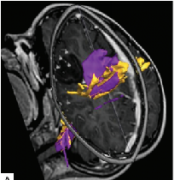

神经导航和神经监测在 癫痫手术 中的应用 (Utility of neuronavigation and neuromonitoring in epilepsy surgery) 英文摘要: The management of medically refractory epilepsy poses b...

我们在加拿大多伦多大学儿童医院(SickKids)引入了脑磁图(MEG)指导的难治性局灶性癫痫儿童癫痫手术。顽固性局灶性 癫痫患儿 的手术候选资格和手术程...